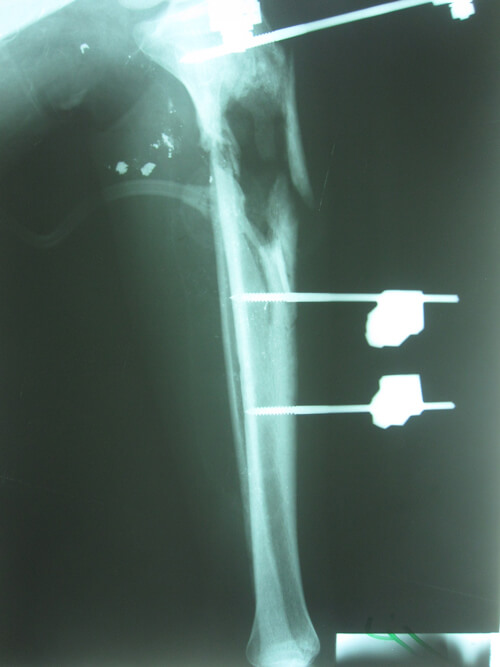

A 20-year-old man presented 46 days after a GSW injury to his right leg. He sustained a Gustilo IIIc fracture of the proximal tibia and fibula with division of the popliteal artery (Figures 13 & 14). The vascular defect was bridged acutely with a vein graft by a vascular surgeon. All toes were necrotic from either acute ischaemia or embolic injury. All compartments below the knee had been affected during the acute ischaemic episode. There was no neural function below the knee: the patient had an insensate foot with a pressure sore on the heel. This equated to a poor foot on an ‘almost dead’ stick.

Figure 13: Right lower leg following compound fracture and vascular injury. The sponge of a vacuum

assisted closure system is still in situ. Extension of the medial wound for access during

acute vascular repair as well as to allow extension as a medial fasciotomy.

Figure 14: Bone loss in the proximal tibial metaphysis.